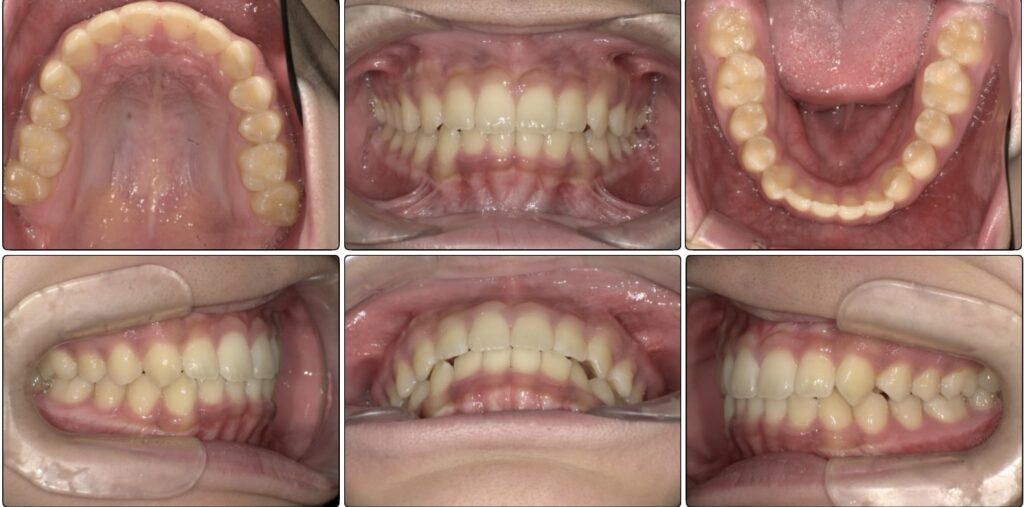

半年後の下の歯の写真です。

がたつきがあったのも綺麗になり、調和の取れた歯並びへ変わってきています!

舌のアクティビティーが少し苦手だったり受験などもあり、3年ほどかかりましたがアクティビティー卒業する頃には綺麗な歯並びになりました!

下の歯もしっかりと見えています。